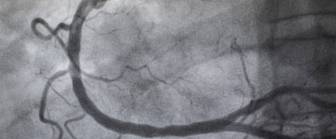

Die Koronar-Angiographie ist eine Untersuchung, bei der die Herzkranzarterien mit Kontrastmittel auf dem Röntgenbild dargestellt werden können. Durch die Methode können Engstellen oder Verlegungen der Herzkranzgefäße diagnostiziert werden. Es handelt sich bei der Koronar-Angiographie um eine Art Herzkatheteruntersuchung.

Zur Koronar-Angiographie wird durch einen Herzkatheter (Linksherzkatheter) ein Kontrastmittel in die Herzkranzarterien gefüllt. Das Mittel kann auf dem Röntgenbild gesehen werden und stellt relativ genau das Innere der Gefäße dar. Somit können Verengungen und auch Verschlüsse sowie manche weitere Veränderungen erkannt werden.

Nach der Entfernung von Draht und Hohlnadel wird ein Kontrastmittel durch den Katheter injiziert, welches dann in die Herzkranzarterien gelangt. Bei dem Vorgang und kurz danach werden Röntgenaufnahmen gemacht. Der Arzt schaut sich diese an und entscheidet, ob im selben Eingriff noch eine Behandlung erfolgen soll.